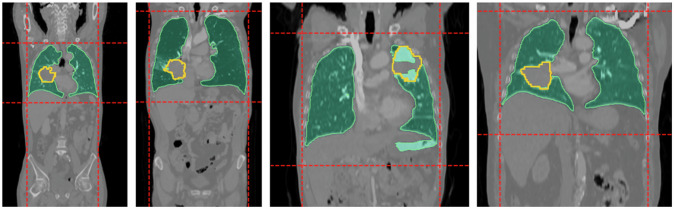

Materials and methods: We analyzed 1,081 retrospectively collected CT scans with 5,322 annotated lesions (4.92 ± 13.05 lesions per scan). The cohort was stratified into training (n = 868) and testing (n = 213) subsets. We developed an automated three-step pipeline, including thoracic bounding box extraction, multi-instance lesion segmentation, and false positive reduction via a novel multiscale cascade classifier to filter spurious and non-lesion candidates.

背景:计算机断层扫描(CT)对肺癌病变的准确分割对于精确诊断、个性化治疗计划和治疗反应评估至关重要。虽然对原发性肺病变的自动分割已经得到了广泛的研究,但对每个患者的多个病变进行分割的能力仍未得到充分的探索。在这项研究中,我们通过引入一种新颖的自动化方法来解决这一差距,该方法用于肺癌病变的多实例分割,利用具有真实世界多中心数据的异质队列。材料和方法:我们回顾性分析了1,081份CT扫描,其中包含5,322个注释病灶(每次扫描4.92±13.05个病灶)。该队列被分为训练组(n = 868)和测试组(n = 213)。我们开发了一个自动化的三步流水线,包括胸围框提取,多实例病变分割,以及通过一种新的多尺度级联分类器过滤虚假和非病变候选物来减少假阳性。结果:在独立测试集上,我们的方法实现了分割的Dice相似系数为76%,病灶检测灵敏度为85%。当在188个真实案例的外部数据集上进行评估时,它的Dice相似系数为73%,病变检测灵敏度为85%。结论:我们的方法在CT扫描上准确地检测和分割了每位患者的多个肺癌病变,在独立测试集和外部真实数据集上显示了稳健性。相关声明:人工智能驱动的病灶分割全面捕捉病灶负担,增强肺癌评估和疾病监测。重点:多实例肺癌病灶自动分割尚未被充分探索,但对疾病评估至关重要。开发了一种基于深度学习的分割管道,训练了多中心真实世界的数据,在外部验证中灵敏度达到85%。胸廓边界盒和假阳性减少技术提高了管道的分割性能。